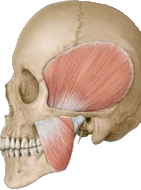

M. pterygoideus lateralis

M. temporalis + M. masseter

Der M. temporalis, M. masseter, M. pterygoideus lateralis und medialis haben eine durchschnittliche Kaukraft von 20-80 Kg. Der Weltrekord liegt bei 430 Kg.